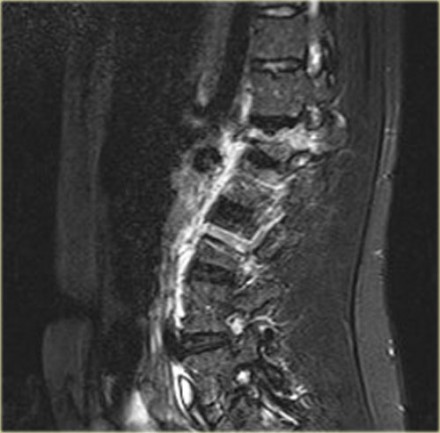

The findings are:

- The morphology is of a vertebral fracture with retropulsion of a fragment, i.e. burst (2 points)

- The PLC is injured with edema of the interspinous ligament and a torn flaval ligament (3 points).

Based on imaging alone, the TLICS score is 5 points and this patient is a surgical candidate.